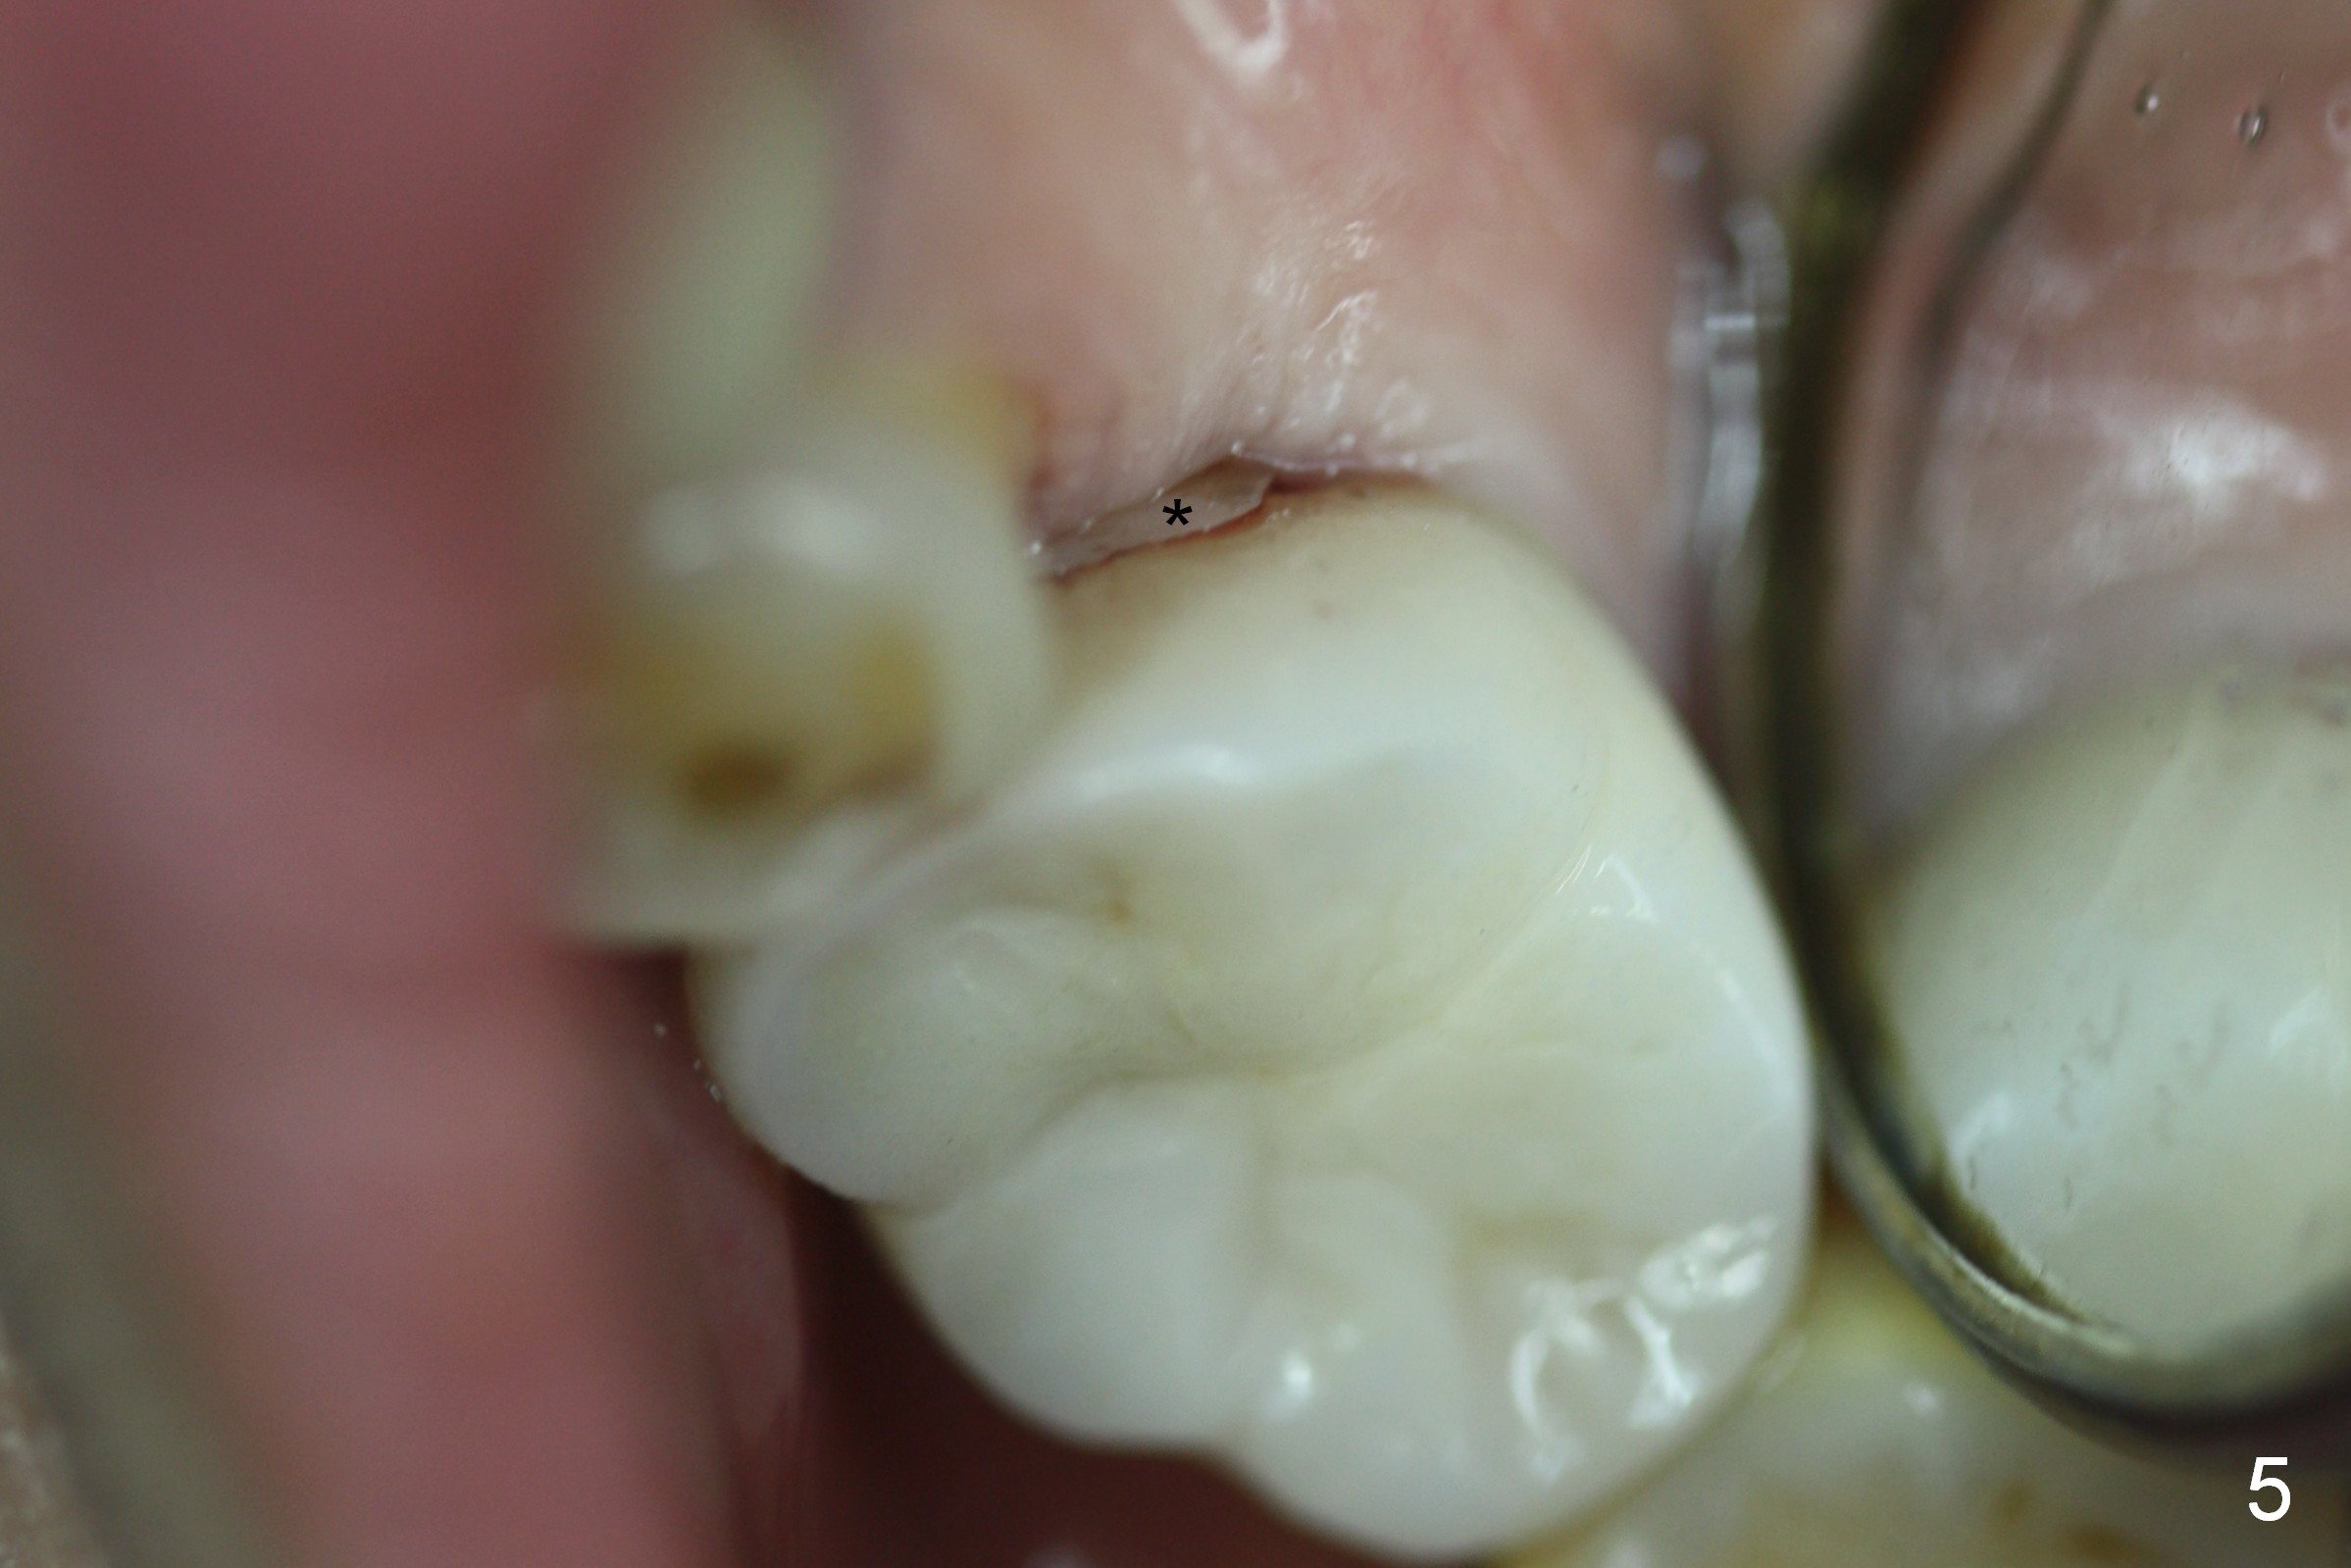

Twenty days later, the patient returns with chief complaint "Top left rubber band is broken". In fact there is no open bite. The crown appears to be completely seated.

Careful examination reveals that there is a fractured piece of porcelain mesiolingual to the crown (Fig.5 *). When the crown is removed, the chip is obvious (Fig.6). In brief, long margin leads to incomplete seating.